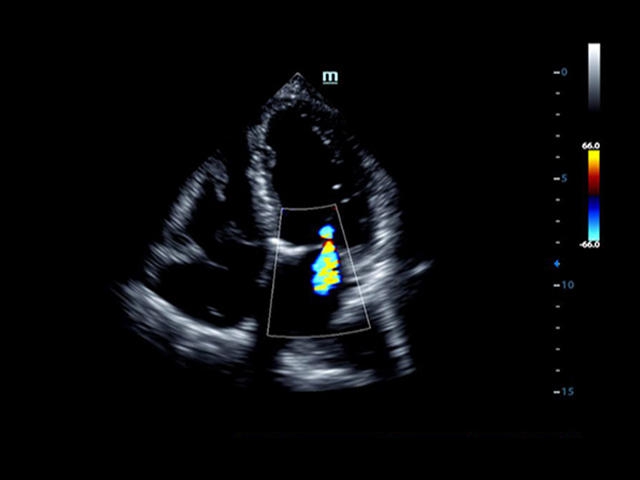

Mindray DC-8 Exp – это ультразвуковой аппарат с архитектурой mQuadro и функцией эластографии Natural Touch. Он оснащен высококлассным 21-дюймовым TFT-монитором с разрешением Full HD. Данный аппарат представляет интерес для специалистов, занимающихся обследованием мягких тканей с использованием эластографии. Режим объемного 4D-сканирования позволяет получать максимально точные диагнозы, сокращая количество неэффективных процедур.

Mindray DC-8 Exp оснащен новым поколением датчиков с увеличенным количеством элементов и инновационной технологией "3T". Это позволяет достичь высокой детализации и качества изображения. Благодаря новейшей технологии iFlow, можно визуализировать даже самые мелкие сосуды и кровеносные пути.

• LVO - опция проведения исследования левого желудочка сердца с применением контрастных веществ;

• TDI (Tissue Doppler imaging, including TDI Color, Power, PW and M mode) - пакет тканевой допплерографии, включая цветное картирование, импульсный тканевой допплер, энергетический тканевой допплер и тканевой М-режим

• LVO - опция проведения исследования левого желудочка с применением контрастных веществ